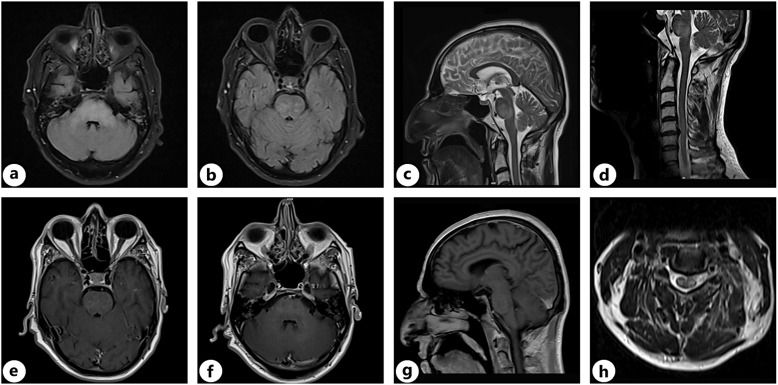

Case presentation: We present 5 patients who received pembrolizumab as a part of their treatment. They exhibited a variety of clinical manifestations, which included central nervous system involvement and necrotizing myopathy, each responding differently to therapeutic interventions. Among the participants, there were two cases of myopathy, one case of demyelinating polyneuropathy, one individual whose myasthenia gravis had worsened, and 1 patient diagnosed with encephalitis. The patients experienced symptoms with varying degrees of severity, leading to different responses in their clinical treatment, and 1 patient ultimately passed away due to complications.